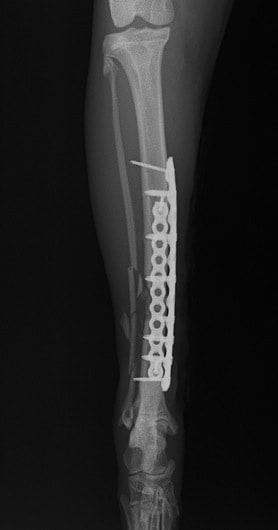

Locking Compression Plate

LCPは、スクリュー(ネジ)とプレート(金属の板)をロックする特殊な構造により骨折部位を固定する新しい世代のプレートシステムです。ひとつのホールでロッキングスクリューとスタンダードスクリューの使用を選択できるユニークな構造をしているため、骨折断端間の圧迫を目的とした従来型プレート固定法に加え、高い角度安定性を有するロッキングスクリューを用いた固定法の選択が可能です。従来のプレートシステムでは困難だった部分の骨折や癒合不全の症例に高い治療効果をもたらします。

Locking compression plate system の特徴

1.骨膜上の血行障害は最小限

2.高い角度安定性

3.プレート設置時の整復位喪失の防止

4.スクリューのルースニング(ゆるみ)の防止

5.コンビネーションホール

6.粗鬆骨における固定性の向上

7.1.5mmと薄いプレートのため、超小型犬にも使用しやすい

8.抜去が不要となることが多い